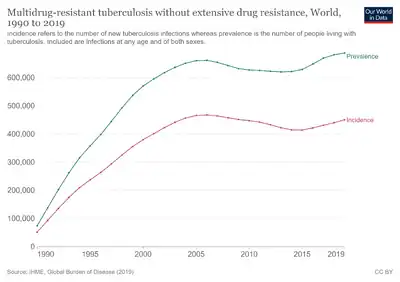

Epidemiology of drug-resistant TB

A 1997 survey of 35 countries found rates above 2% in about a third of the countries surveyed. The highest rates were in the former USSR, the Baltic states, Argentina, India and China, and was associated with poor or failing national Tuberculosis Control programmes. Likewise, the appearance of high rates of MDR-TB in New York city the early 1990s was associated with the dismantling of public health programmes by the Reagan administration.[74][75]

MDR-TB can develop in the course of the treatment of fully sensitive TB and this is always the result of patients missing doses or failing to complete a course of treatment.

Thankfully, MDR-TB strains appear to be less fit and less transmissible. It has been known of many years that INH-resistant TB is less virulent in guinea pigs, and the epidemiological evidence is that MDR strains of TB do not dominate naturally. A study in Los Angeles found that only 6% of cases of MDR-TB were clustered. This should not be a cause for complacency: it must be remembered that MDR-TB has a mortality rate comparable to lung cancer. It must also be remembered that people who have weakened immune systems (because of diseases such as HIV or because of drugs) are more susceptible to catching TB.